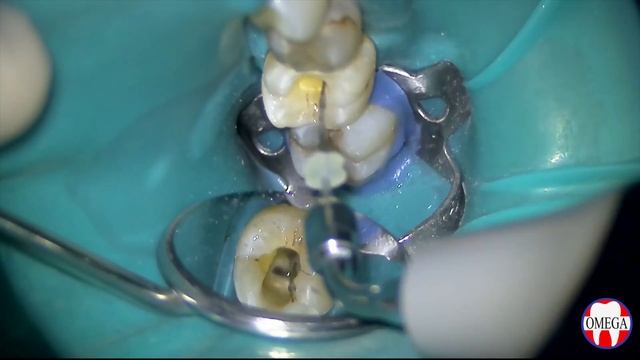

Подробно рассказываем о таблице Менделеева и ее значении для науки. Узнаем, есть ли вероятность происхождения химических элементов из других систем. Какой след оставил Луна-25 на поверхности Луны? Разбираемся в тайнах космических аппаратов и метеоритных кратерах. #ТаблицаМенделеева #ТайныХимическихЭлементов #Луна25 #МетеоритныйКратер #КосмическиеАппараты #Химия #Наука #ТаблицаМенделеева #ЛуннаяПоверхность #НаучнаяТеорияVi gjorde en tolkning av ASAP sience på våra bild lektioner och detta är resultatet. Enjoy 😊Адрес: Уральская 74Dr. Karlis Ullis, a renowned doctor in sports and anti-aging medicine, during an interview with www.youngbodymind.com, talks about the breakthrough of stem cells technologies.#Cricket #ipl #india #tamilnaduÜç Kız Kardeş 82. Bölüm Fragmanı | ACI CENAZE! Herkese merhaba arkadaşlar ben Aras. Bu videoda sizlere Üç Kız Kardeş dizisinin yeni bölümü hakkında analiz yaptım ve yorumlarımı sizlerle paylaştım. NOT : Bu Bir ANALİZ VE TAHMİN videosudur.Cочетанное применение Soco SC Pro , ProGlider и ProFile файлов📣 Direkt zum Magnesium-RESTOCK: 👉 https://gannikus-original.de/products/magnesium-stack-kapseln 🐟 OMEGA BACKUP jetzt bestellen: 👉 https://gannikus-original.de/products/omega-backup-kapseln-gross 🏋🏼♂️ CREA BETA Stack wieder im Sortiment: 👉 https://gannikus-original.de/products/crea-beta-stack-creatin-beta-alanin-pulver 💤 SOMNIA (Nr. 1 Schlaf-Supp) back in stock: 👉 https://gannikus-original.de/products/somnia-schlafdrink 💪 GALENIKUS Pump wieder in allen Flavours verfügbar: 👉 https://gannikus-original.de/products/galenikus-pump 🚨 GANNIKUS Original Verum Whey zurück auf Lager: 👉 https://gannikus-original.de/products/verum-whey-protein 💣 Jetzt GALENIKUS, den besten EU-Booster, in 3 Flavours sichern: 👉 https://gannikus-original.de/products/galenikus-booster ✅ Bei GANNIKUS Progress Coaching anmelden: 👉 https://gannikus-coaching.comGiven the following limiting molar conductivies at `25^(@)C,, Hcl, 426Omega^(-1)cm^(2)mol^(-1),NaCl, 126Omega^(-1)cm^(2)mol^(-1),NaC`(sodium crotonate) ,`83Omega^(-1)cm^(2)mol^(-1)`. What is the ionization constant of crotonic acid? If the conductivity of a `0.001M` crotonic acid `(HC)` solution is `3.83xx10^(-5)Omega^(-1)cm^(-1)`?Dalam sesi ini, saya menceritakan serba sedikit beberapa perkara tentang IPO 1)Apakah itu IPO? 2)Bagaimana nak apply IPO melalui MITI ? Tips and Tricks 3) Gambaran awal tentang syarikat Volcano. (Boleh skip ke minit 39:00) -Tujuan nak diIPOkan -Business syarikat Volcano -Propekktus syarikat --------------------------------- Boleh PM saya di telegram jika berminat dengan perkara di bawah: https://t.me/dramer94 Boleh juga follow channel saya di telegram : https://t.me/streetraders untuk perkongsian tentang saham :) 1)Nak buka akaun CDS ? Saham a) Mplus dan CIMB bersama iSaham dan dapat screener iSaham premium dan support group iSaham percuma b) RHB bersama team AAA(Asri Ahmad Academy ) dan dapat channel support dengan weekly live revision c) UOB Komoditi (FCPO) -RHB ,Philip Futures dan LT 2) Nak Invest dalam Interpacific Private Mandate dibawah seliaan Fund Manager Dato' Dr Nazri Khan (DDNK)? -Minimum Investment 50k -Syarikat Interpac dimiliki oleh Berjaya Group di bawah Tan Sri Vincent Tant 3) Nak belajar tentang Saham? -Silibus basic hingga advance -Lifetime group support - Undervalue price -For more details and registration boleh klik link ni : https://traderjalanan.onpay.my/order/form/1 Jangan lupa untuk share,like dan subscribe video ini ! Nantikan lebih banyak perkongsian tentang saham dalam video seterusnya!http://demonstrations.wolfram.com/LengthWidthAndHeightOfAnImpossibleObject/ The Wolfram Demonstrations Project contains thousands of free interactive visualizations, with new entries added daily. Mathematica is a very nice tool for building three-dimensional objects and to observe them from different viewpoints. From certain viewpoints, some objects look impossible. This Demonstration shows such an object, which is made of square beams that are ... Contributed by: Bernard VuilleumierLittle Anna puts on a show with Peace Fleece's Russian Waldorf Ice Theater! Here are the words to the song in English and Russian: Once there was a grandma Who had two merry geese One was grey and the other was white Two very merry geese One was grey and the other was white Two very merry geese! The geese washed their feet In a puddle by a ditch One was grey and the other was white They hid in a ditch! One was grey and the other was white They hid in a ditch! The grandma is crying: "I have lost my geese! One was grey and the other was white Geese, my dear geese! One was grey and the other was white Geese, my dear geese!" Then, the geese came out They bowed to the grandma One was grey and the other was white They bowed to the grandma! One was grey and the other was white They bowed to the grandma! Жили у бабуси Два весёлых гуся, Один - серый, другой - белый, Два весёлых гуся. Один - серый, другой - белый, Два весёлых гуся! Мыли гуси лапки В луже у канавки, Один - серый, другой - белый, Спрятались в канавке. Один - серый, другой - белый, Спрятались в канавке! Вот кричит бабуся: «Ой, пропали гуси! Один - серый, другой - белый, Гуси мои, гуси! Один - серый, другой - белый, Гуси мои, гуси!» Выходили гуси, Кланялись бабусе, Один - серый, другой - белый, Кланялись бабусе. Один - серый, другой - белый, Кланялись бабусе!Cara mudah membuat bor mini dari dinamo bekas dvd, rumayanlah dari pada beli bisa kita manfaatkan :) hehe.... Bahan / komponen : 1. Dinamo Bekas DVD. 2. Sambungan Pipa PVC 1/4. 3. Kontak ON / OFF. 4. Chuck Drill / Kepala Bor mini. 5. Adaptor DC. . . . . Bingung cari Kado / hadiah ulang tahun, anniversary, / souvenir yang unik, dan keren?? . ⬇️⬇️⬇️⬇️⬇️⬇️⬇️ . Lukisan bakar bisa jadi pilihan!! 💖 Kunjungi akun instagram @handproject7 https://instagram.com/handproject7?igshid=owvntm80wz2q ============================================================= . . . . Semoga video-video yang saya upload bisa bermanfaat. :) . . ============================================================= SELALU SUPPORT CHANNEL INI DENGAN SUBSCRIBE - LIKE - COMMENT & SHARE, TERIMAKASIH SUDAH MENONTON.!!! . Selamat mencoba :) #bormini #dinamodc #diy #craft #handmade #dirumahaja #dinamodvd #samasayaVideo Tribute for Raven, from Teen Titans, music by Dark Tranquillity, "Lethe"IPL Points Table 2024 Today 24 APRIL | Chennai Lucknow after match points table | IPL 2024 #ipl #ipl2024 #iplhighlights2024 #iplpointstable2024 #iplpointtable #pointstable #chennaisuperkings #royalchallengersbangalore #delhicapitals #gujarattitans #kolkataknightriders #lucknowsupergiants #mumbaiindians #punjabkings #rajasthanroyals #sunrisershyderabad #Csk #Kkr #Lsg #Mi #Rcb #Dc #Pbks #Rr #Srh #gt #pointstable Chennai Super Kings Royal Challengers Bangalore Delhi Capitals Gujarat Titans Kolkata Knight Riders Lucknow Super Giants Mumbai Indians Punjab Kings Rajasthan Royals Sunrisers Hyderabad Csk,Kkr,Lsg,Mi,Rcb,Dc,Pbks,Rr,Srh,Gt today ipl match points table 2024 today ipl match live points table 2024 match points table 2024 ipl match points table 2024 today ipl points table 2024 today match ipl points table 2024 today match list today ipl match highlights 2024 points table today match points table 2024 today match points table ipl today match points table ipl 2024 ipl points table 2024 points table ipl 2024 ipl 2024 points table Chennai Super Kings vs Lucknow Super Giants match kaun jita CSK vs LSG match cal ka match kaun jita CSK vs LSG match kaun jita Chennai Lucknow ka match kaun jita CSK vs LSG 2024 highlights CSK vs LSG cal ka match kaun jita ipl kal ka ipl match CSK vs LSG kal ka match kon jeeta kal ka match highlight 2024 ka ipl kaun jita CSK vs LSG kon jeeta cal ka match cal ka ipl match kon jita kal ka match kaun jeeta aaj ka ipl match kon jita aaj ka match CSK vs LSG ipl match CSK vs LSG highlights Chennai Lucknow highlights CSK vs LSG live score CSK vs LSG live cal ka match kaun jita Chennai Super Kings vs Lucknow Super Giants mein se kaun jita Marcus Stoinis ki batting today ipl points table 2024 ipl points table, ipl points 2024 pl points table live, ipl points table 24 ipl points chart ipl points table update, ipl points table new, ipl points table 2024 today, ipl points, ipl points table today ipl live match today00:00 Tizer 00:50 Kirish 03:19 "O'z haq huquqini talab qilib chiqacdigan blogerlar judayam kam" 05:02 "Halovatimni yo'qotib qo'ydim" 11:34 Men davlat xodimi bo'lishni istamayman" 12:29 Ozod fikr va ozod haraktni xoxlayman 16:03 "Bu bola terpila" 19:36 "Bir yilga $ 350.000 teklif qilishdi" 21:30 "Xalqga foydasi tegadigan" nom bilan bu dunyoda iz qoldirish 23:08 Qilayatotgan ishimga "fatvo" olganman 32:01 O'lim siz uchun nima? 33:08 Millat siz uchun nima? 34:34 O'zbekistonda bir narsanı o'zgartirishni ioji bo'lganda u nima va qay tarzda bo'lar edi? 35:24 "Odamlar juda ko'p narsadan qo'rqishadi"Děkuji všem za podporu moc si toho vážím Přímá podpora 670100-2209270000/6210Видеого лайк менен колдоп 👍Каналга катталыныздар 🔔